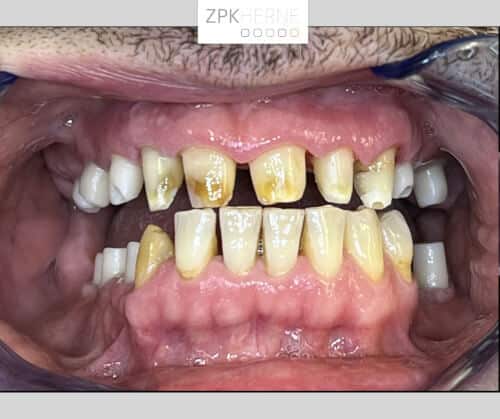

Über ein Jahrzehnt lang hat die Furcht vor dem Behandlungsstuhl unseren Patienten von dem dringend notwendigen Zahnarztbesuch abgehalten. Dabei leidet er fast schon ebenso lange unter einem nicht voll funktionsfähigen Gebiss: Seit mehreren Jahren fehlen ihm im Unter- sowie im Oberkiefer jeweils ab dem Eckzahn einige Zähne. Außerdem ist die Bisshöhe abgesackt, das heißt seit Jahrzehnten knirscht sich der Patient die Zahnsubstanz herunter. Das führt unter anderem dazu, dass er nicht mehr vernünftig essen kann. Hierfür wünscht er sich eine neue festsitzende Versorgung mittels Implantate.

Nach der gründlichen Anamnese werden aktuelle 3D-Aufnahmen der Gebisssituation erstellt. Dabei kommt das Team um Herrn Dr. Mintert zu den folgenden Ergebnissen und Handlungsschritten: